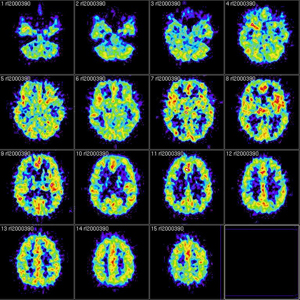

Una nueva investigación publicada en línea por primera vez en The Lancet Neurology se destacan los de largo plazo las secuelas de meningitis en los niños. El estudio, dirigido por el profesor Russell Viner en el Instituto UCL de Salud Infantil, muestra que 1 de cada 3 niños que han sufrido la enfermedad meningocócica del grupo B (MenB), el tipo más común de meningitis bacteriana en el Reino Unido, se quedará con tras-efectos.

La meningitis bacteriana y septicemia afecta a alrededor de 3.400 personas en el Reino Unido cada año, y aproximadamente la mitad (1.700) de ellas son niños. La nueva investigación, encargada por la organización benéfica nacional Meningitis Trust, miró a la carga cognitiva y psicológica de MenB, así como las principales discapacidades físicas y neurológicas en niños de tan sólo tres años de edad.

Las víctimas resultaron ser significativamente más propensos a experimentar problemas de salud mental que uno de cada cinco o ansiedad que sufren trastornos del comportamiento. Además, la meningitis se encontró un impacto en la memoria a largo y corto plazo de una persona-y dejar sobrevivientes significativamente más probabilidades de sufrir epilepsia. El estudio también identificó los posibles problemas de aprendizaje.

Los niños víctimas pueden quedar con un bajo coeficiente intelectual limítrofe, dejando detrás de ellos en el aula y que podría limitar su nivel de instrucción. Ellos son cinco veces más propensas a tener problemas en el habla y la comunicación, y más tarde en la vida escolar función ejecutiva display pobres que afectan a su capacidad de planificar y organizar, sobre todo cuando pasan de primaria a secundaria. Junto con el «oculto» secuelas, el impacto devastador física de meningitis se informó, con los enfermos que son cinco veces más propensos a tener problemas de audición significativa, con el 2,4% de los sobrevivientes que tienen pérdida auditiva bilateral que requiere un implante coclear. Además, la amputación significativa con discapacidad fue presenciado.

El investigador principal, el profesor Russell Viner en el Instituto UCL de Salud Infantil, dijo: «MOSAIC es el primer estudio exhaustivo de los resultados de la enfermedad meningocócica del serogrupo B publicado en cualquier parte del mundo, es también el mayor estudio de los resultados de la enfermedad meningocócica nunca. publicado. La alta calidad y la importancia de los datos han sido reconocidos por la aceptación por la vía rápida publicación en la prestigiosa revista internacional The Lancet Neurology. medida que los gobiernos de todo el mundo comienzan el proceso de decidir si introducir nuevas vacunas MenB, el mosaico datos juegan un papel central en informar a estas decisiones «.